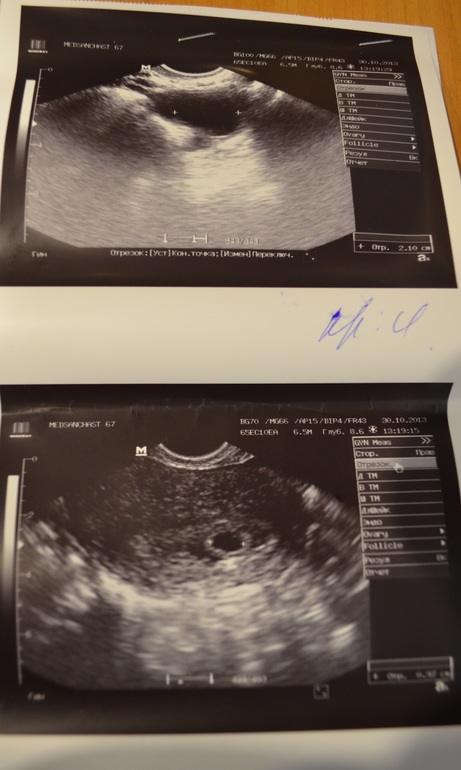

наше первое УЗИ

Сегодня первый раз была у гинеколога, там же сделали первое узи и подтвердили маточную беременность) Так обрадовалась, что все у нас хорошо, что и забыла все вопросы, которые хотела врачу задать) Она сказала, что все хорошо и в норме, а я сейчас в инете стала рыться и мне кажется, что все у нас маленькое какое-то(( плодное яйцо 9,7мм, КТР 3,5мм, 5-6 неделя(акушерская) , сердцебиение не отчетливое... А еще на снимке УЗИ никаких белых пятнышек не видно, доктор сказала, что просто дитёнок к стеночке прижался (на снимке справа) по этому и не видно((

Сегодня первый раз была у гинеколога, там же сделали первое узи и подтвердили маточную беременность) Так обрадовалась, что все у нас хорошо, что и забыла все вопросы, которые хотела врачу задать) Она сказала, что все хорошо и в норме, а я сейчас в инете стала рыться и мне кажется, что все у нас маленькое какое-то(( плодное яйцо 9,7мм, КТР 3,5мм, 5-6 неделя(акушерская) , сердцебиение не отчетливое... А еще на снимке УЗИ никаких белых пятнышек не видно, доктор сказала, что просто дитёнок к стеночке прижался (на снимке справа) по этому и не видно((